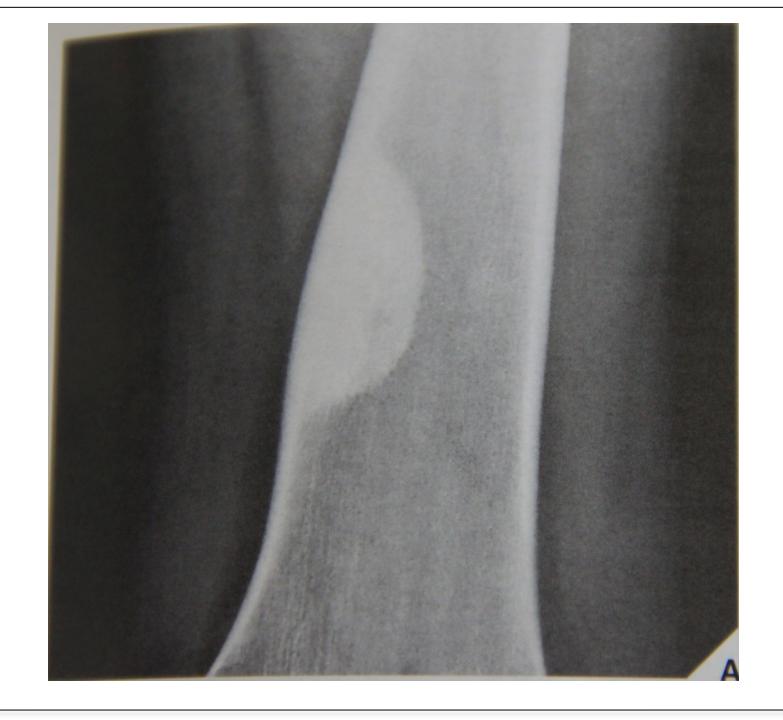

Osteoid Osteoma

Thick cortex